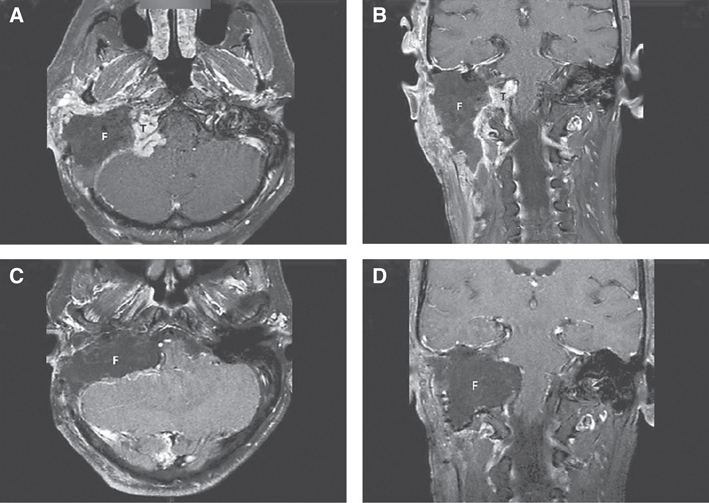

A large intradural extension can be managed either by a single-stage or by a two-stage surgery (24). Our experience has shown that a planned second-stage resection may be preferable in case of extensive dural involvement. The advantage of two-stage surgery is that a clear plane of dissection can be established between the tumor and the brain stem due to the devascularization of the tumor after the first-stage surgery and subsequent shrinkage of the intradural mass (Figure 4A–D). Another reason for staging the surgery is the argument that LCNs involved with tumor would need to be sacrificed, resulting in severe cough. This would lead to an increase in intracranial pressure facilitating cerebrospinal fluid leaks (40). We prefer to stage surgery when tumors have over 2 cm of intradural extension. For the second stage, a petro-occipital-trans-sigmoid (POTS) approach is preferred, but a modified transcochlear approach or an enlarged translabyrinthine approach may also be used.

Fig 4

Figure 4 Imaging. (A and B) MRI, axial, and coronal views after the first-stage surgery. The residual intradural tumor is noted. The surgical defect is filled with abdominal fat. (C and D), MRI, axial, and coronal views after the second-stage surgery. After the surgery, there is no residual tumor. F, fat; T, intradural tumor.